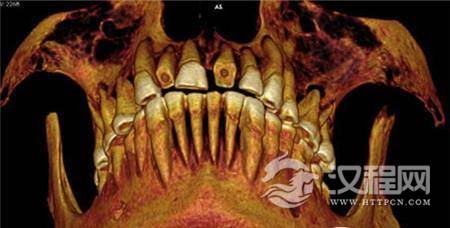

《古病理学国际期刊》的文章称,来自加拿大西安大略大学的安德鲁·韦德利用一种新型高分辨率CT仪扫描木乃伊的牙齿和身体,并且根据扫描片重建了3D图以进行更为细致的研究。从CT扫描片可以看到,木乃伊的一颗牙齿龋洞里塞着一块亚麻布团。这块亚麻布之前可能经过无花果汁液或雪松油等药物的浸泡,随后被塞入下颚第一、二颗臼齿中间,也就是最大、也是最疼的龋洞里。这么做既能起到抵挡食物残渣进入龋洞的屏障作用,又能利用亚麻布上的药物缓解疼痛。

研究人员介绍说,这是已知的首例古埃及牙齿填充疗法,“坝基补缝填坑处理,是指在相邻两颗牙齿较大的龋洞里填补防护物,一般是用药物填充。而设置屏障保护是古埃及牙科治疗的独特案例。这个案例中的牙科填充处理是迄今为止古埃及木乃伊研究中很独特的,也是极少数记录在册的古埃及牙科干预措施中的一种。”